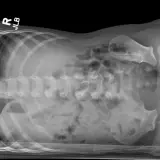

Over 2,100 interactive radiology cases, curated by radiologists for your level of training. Scroll, window, and view cases full screen — just like on PACS. Click linked findings in each writeup to jump straight to them on the image. Cases include sample reports, a focused discussion section, original illustrations, and videos.

Des cas entièrement interactifs avec les outils attendus d'un PACS — défilement, fenêtrage, zoom, déplacement, mesures, ROI et mode plein écran.

Des annotations détaillées mettent en évidence les résultats clés directement sur les cas. Cliquez sur les résultats liés dans les descriptions de cas pour accéder à leur emplacement exact sur l'examen.